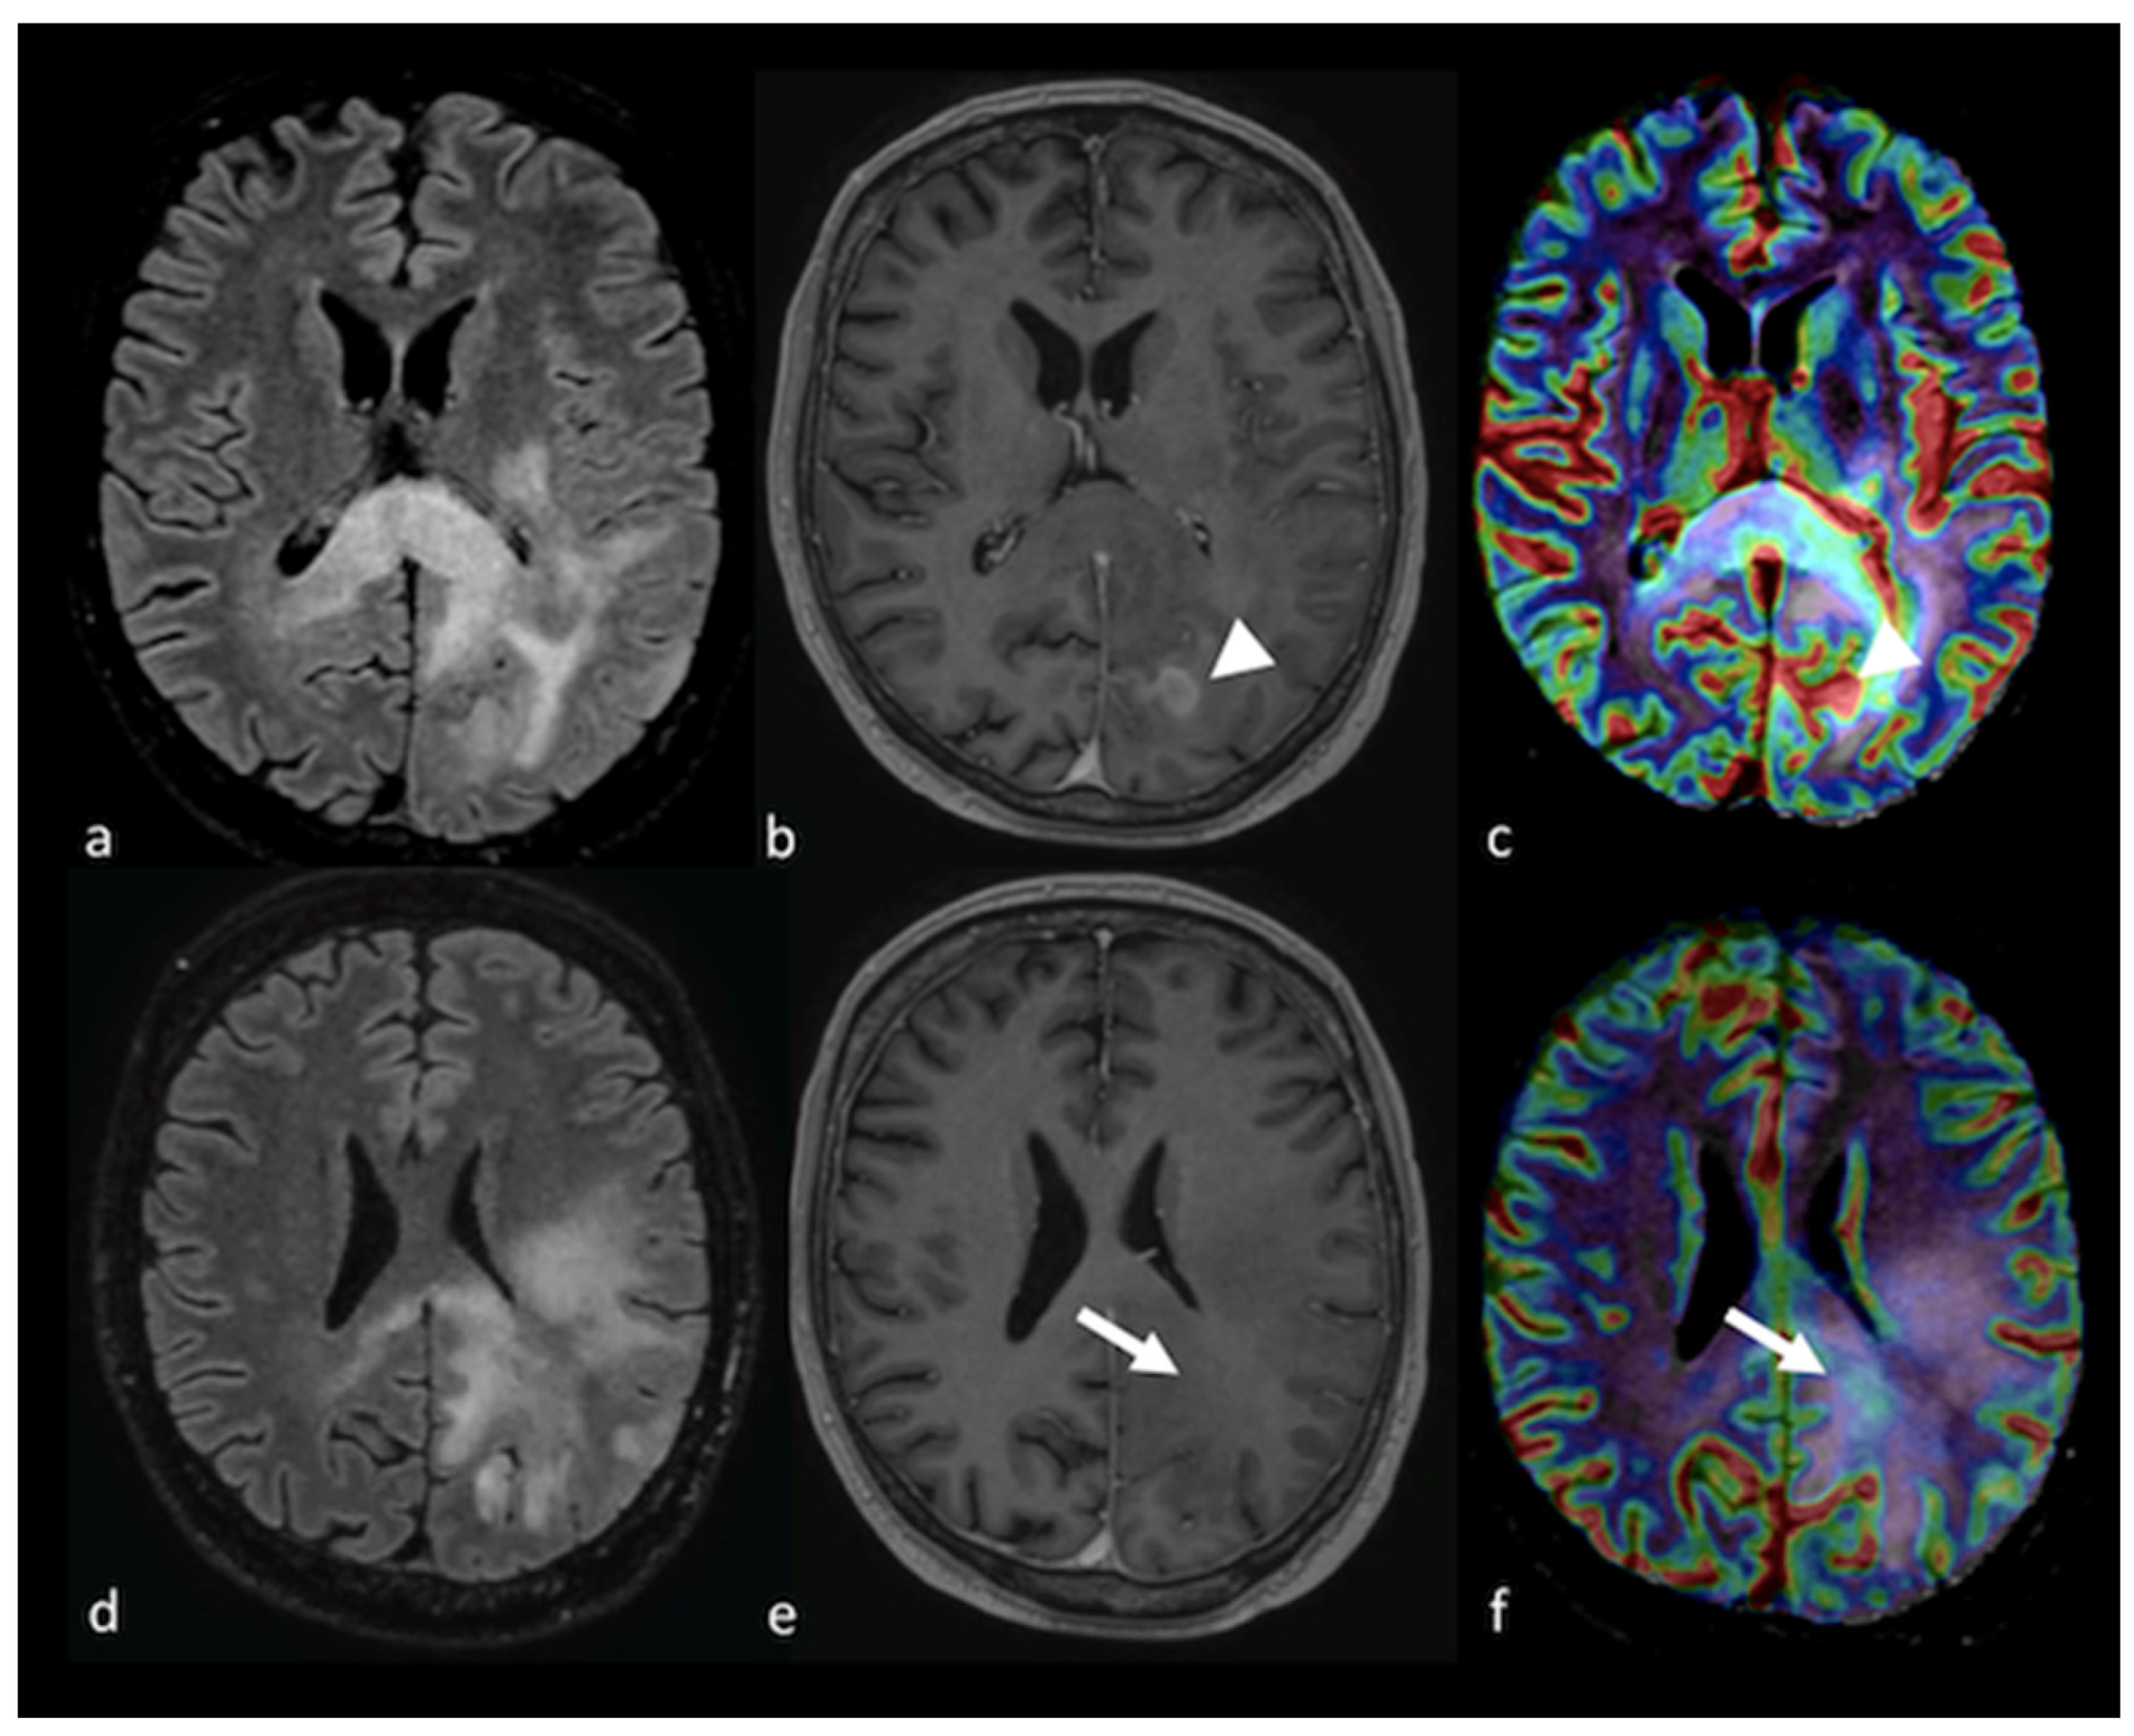

3.2.1. Diffusion-Weighted Imaging (DWI)

3.2.2. Diffusion Tensor Imaging (DTI)